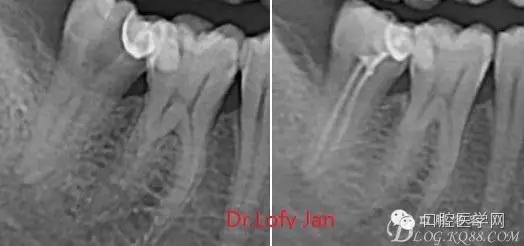

①有助于發(fā)現(xiàn)牙體和根尖周組織的異常改變,如牙折、牙內(nèi)吸收、髓腔鈣化及根尖囊腫;

②有助于確定牙根和根管的數(shù)目、位置、形態(tài)、方向和彎曲情況;

③有助于了解以前曾作過的治療情況,為再治療提供依據(jù);

④在操作前估計(jì)根管的工作長度;

⑤評價(jià)根管充填的質(zhì)量以及療效。